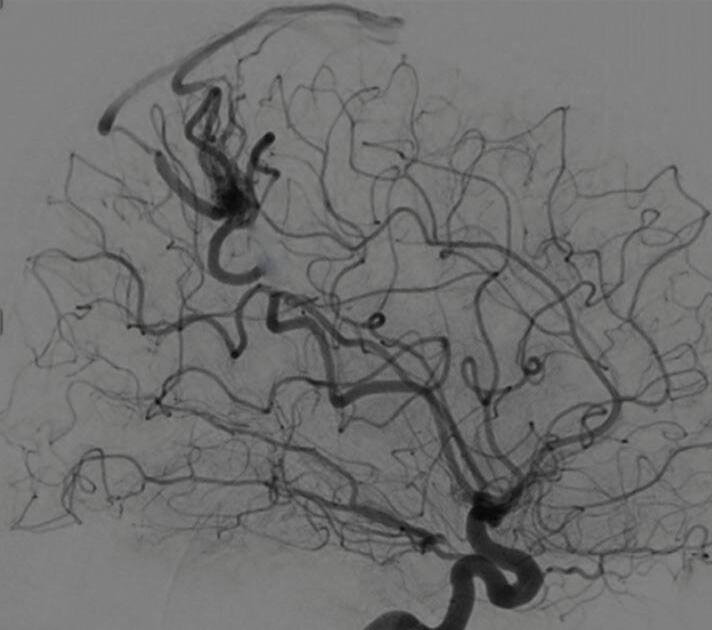

Fig. 1-9. RNM T2 em cortes (a) axial e (b) sagital. (c,d) Tractografia axial – sagital, demonstrando a posição de uma MAV não rota localizada na superfície basal do lobo frontal, nos giros orbitários e reto à direita (setas longas). Arteriografia digital cerebral com injeção de contraste via carótida direita, (e) AP e (f) em perfil demonstrando MAV nutrida por ramos da artéria cerebral média e cerebral anterior direita e drenagem para o seio sagital superior (seta curta).